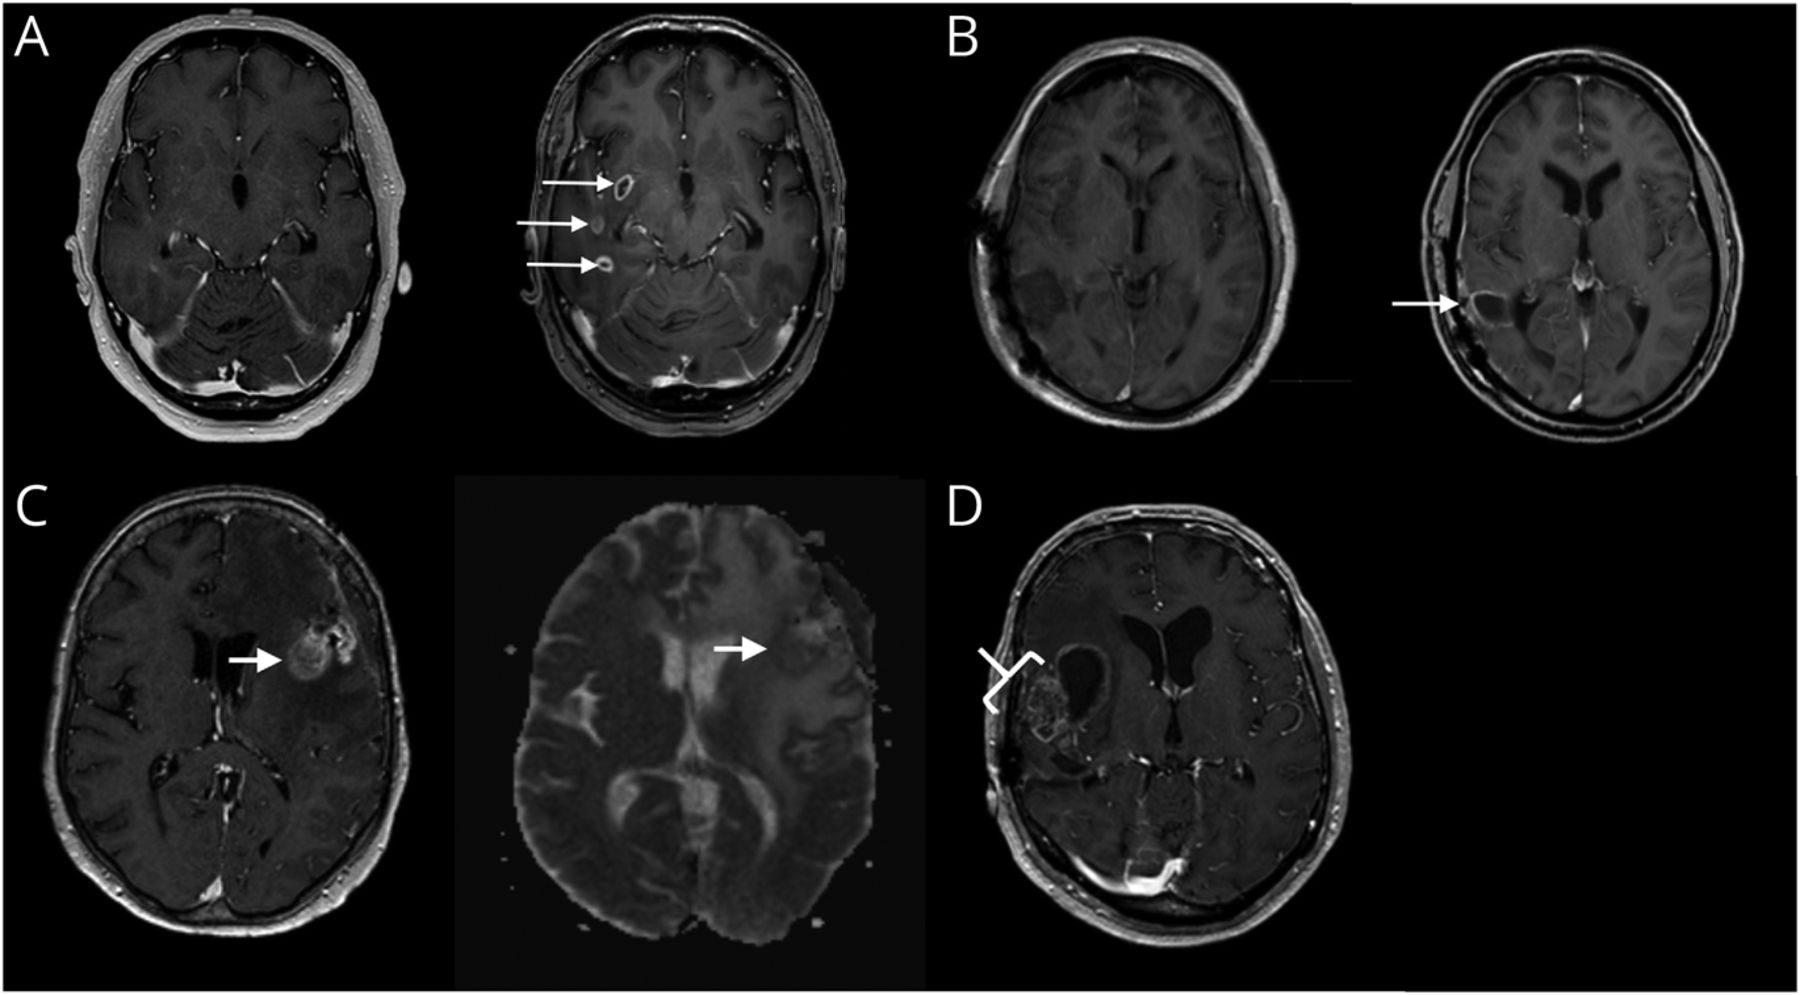

以下特点从比较基线和检索过程扫描:肿瘤的比例增长,新的增强,14,15多个新的增强,12,16增加边际外科腔周围的增强,15新结节性增强,14,- - - - - -,16新胼胝体的增强,12,14,- - - - - -,16新的或增强透明隔,增加12新的或增加室增强,12,- - - - - -,16增加,稳定,或减少质量效应,天赋异常。室增强被定义为渗透到心室的边界。14质量效应是在沟的变窄的情况下,压缩心室或中线的转变。以防多个新的或增加充当病变进展扫描检测,这些病变都分开了。所有关于肿瘤大小与RANO标准进行测量20.并指出单独为每个病变。显示在重要的MRI特征图1和无意义的MRI特点是聚集在eFigure 1 (links.lww.com/WNL/B943)。

(A)一个64岁的男子与一个异柠檬酸脱氢酶(IDH)野生型(WT)胶质母细胞瘤放疗治疗。左:MRI术前基线。右:随访MRI(基线后93天)与多个新的对比增强。(B)一个58岁的男人IDH-WT胶质母细胞瘤与temozolomide-based放化疗治疗。左:基线MRI切除后手术腔。右:随访MRI(基线后91天),增加手术腔的边缘增强。(C) 65岁的女人胶质母细胞瘤,IDH状态未知,接受放射治疗。左:T1-MRI造影剂。右:Isointense ADC信号与健康的白质。(D) 66岁的男子与一个IDH-mutated星形细胞瘤4级处理temozolomide-based放化疗:肥皂泡增强(小区域坏死17)。